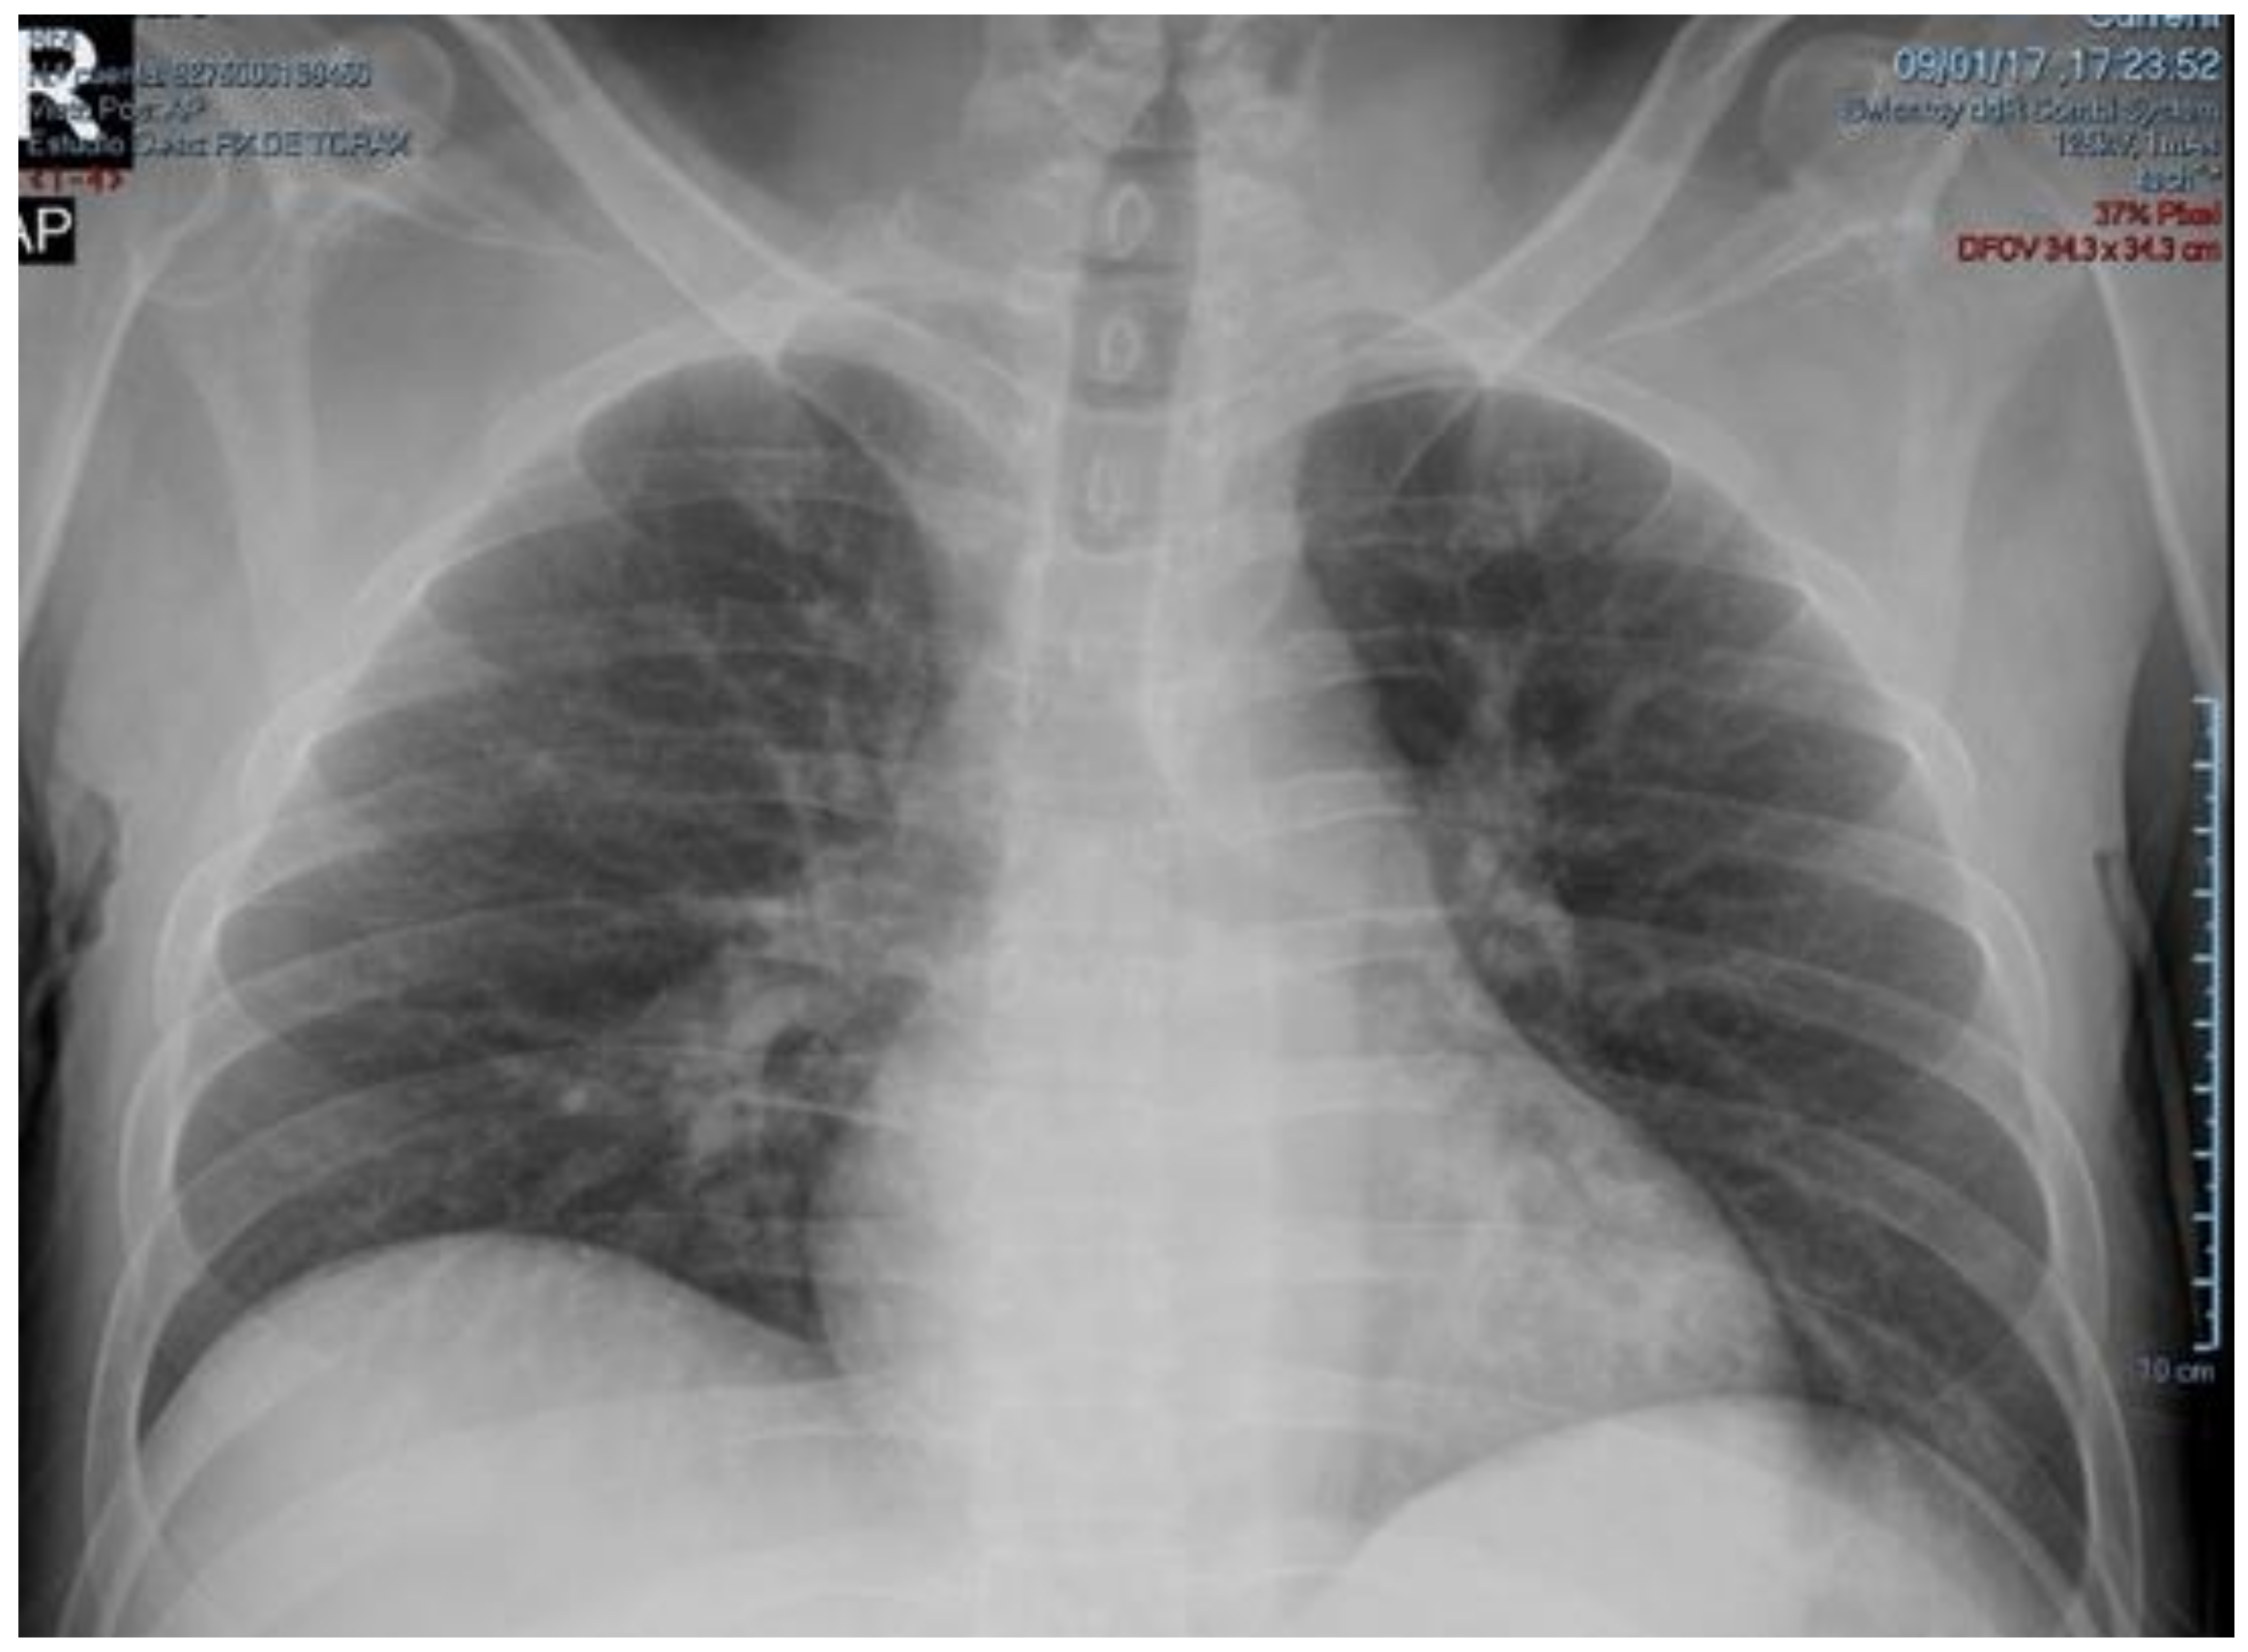

2. Case Presentation